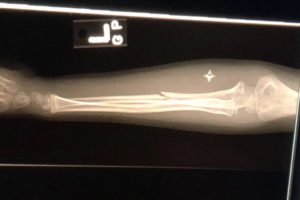

A broken arm doesn’t always look broken.

Our son’s arm was straight and had no visible bruising. He didn’t complain about it hurting terribly. It wasn’t until we observed that he had lost full mobility of his arm— he couldn’t touch his shoulder— that we realized we needed to get it checked out as something more than just your average fall. When in doubt, head to the Emergency Room.